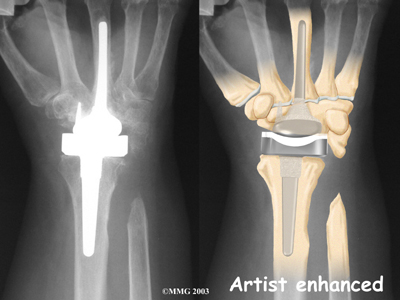

Modern artificial wrist joints are made of metal and plastic. The part that fits against the end of the radius bone of the forearm is called the radial component. It is made up of two pieces. A flat metal piece is placed on the front part of the radius. It has a stem that attaches down into the canal of the bone. A plastic cup fits onto the metal piece, forming a socket for the artificial wrist joint.

The part that replaces the small wrist bones is called the distal component. This piece is made completely of metal. It is globe shaped to fit into the plastic socket on the end of the radius. The metal distal component is attached by two metal stems that fit into the hollow bone marrow cavities of the carpal and metacarpal bones of the hand.

The plastic used in artificial joints is tough and slick. It allows the two pieces of the new joint to glide easily against each other as you move your wrist. The ball and socket allow movement of the wrist in all directions.

Replacement Joint

Cemented into Place